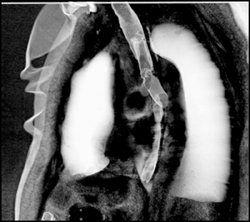

Right Lung Transplant With Patent Right Mainstem Bronchus